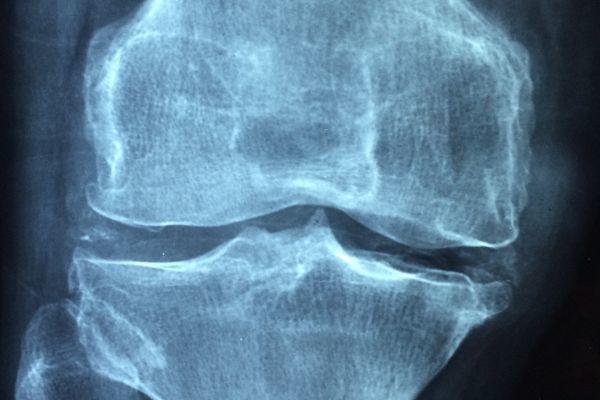

L’artrite è caratterizzata da un’infiammazione cronica delle articolazioni e si manifesta con dolore, gonfiore e rigidità funzionale. Tende a peggiorare in condizioni di riposo.